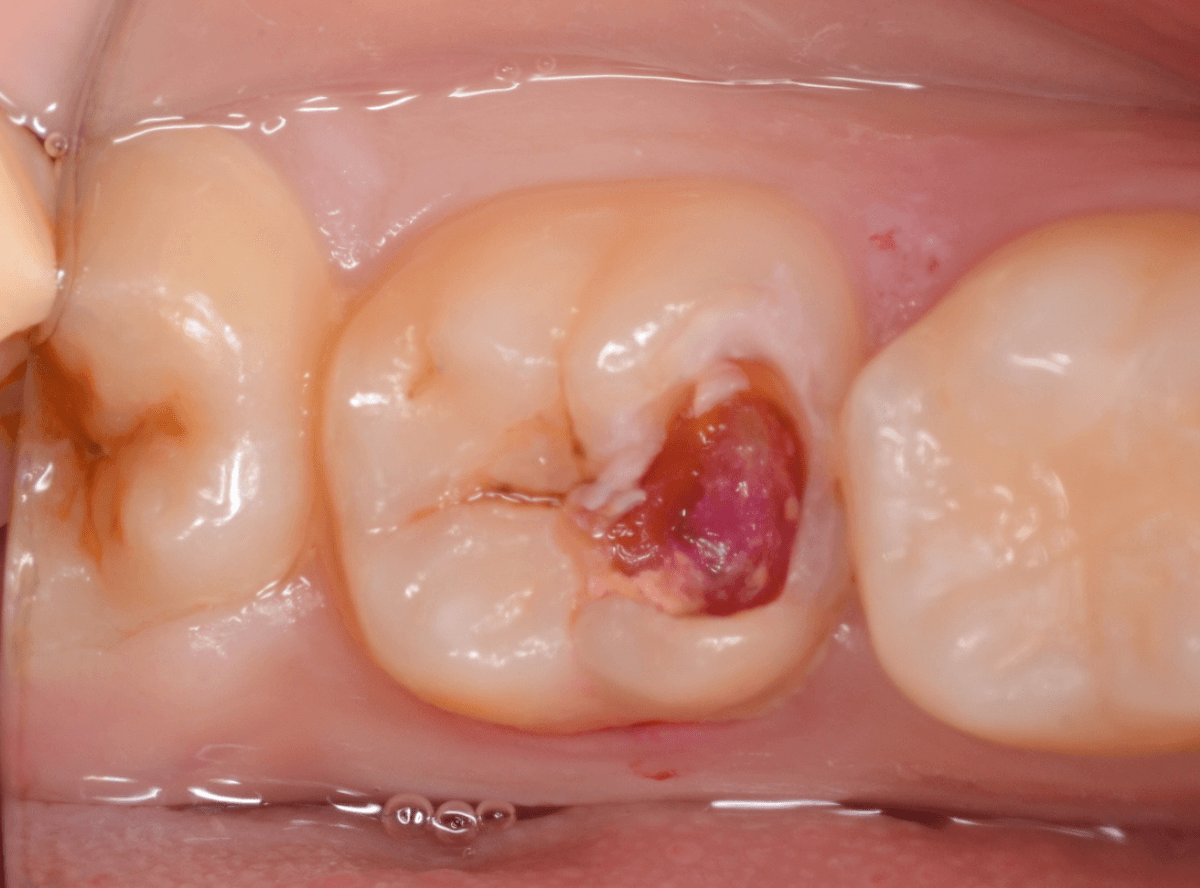

Case.14 CR(コンポジット・レジン)の下の深い虫歯

奥歯で咬んだ時に、痛みを感じるという訴えで来院された患者さんです。

パッと見は特に問題なさそうな状態ですが、大きなレジン治療がしてあり、レジンの奥もボヤっと黒っぽく見えてアヤシイ感じです。

麻酔をして、治療を開始します。

レジンを外すと、中から出血してきました。

これは、歯のスキマに歯肉が入り込んでしまったために起こってしまったものです。

おそらく、随分前から虫歯が進行していたと思われます。

止血しながら、電気メスで歯の中に入り込んだ歯肉を除去します。

虫歯と入り込んだ歯肉でぐちゃぐちゃになっている状態でした。

これでは、痛みが出てもおかしくありません。

慎重に全ての虫歯を除去したところです。

〇部が神経の入り口が見えているところです。

神経を保護する処置をして、しばらく経過観察しますが、痛みが出て神経を除去する必要が出る可能性も高いです。

痛みが出ませんように・・・。